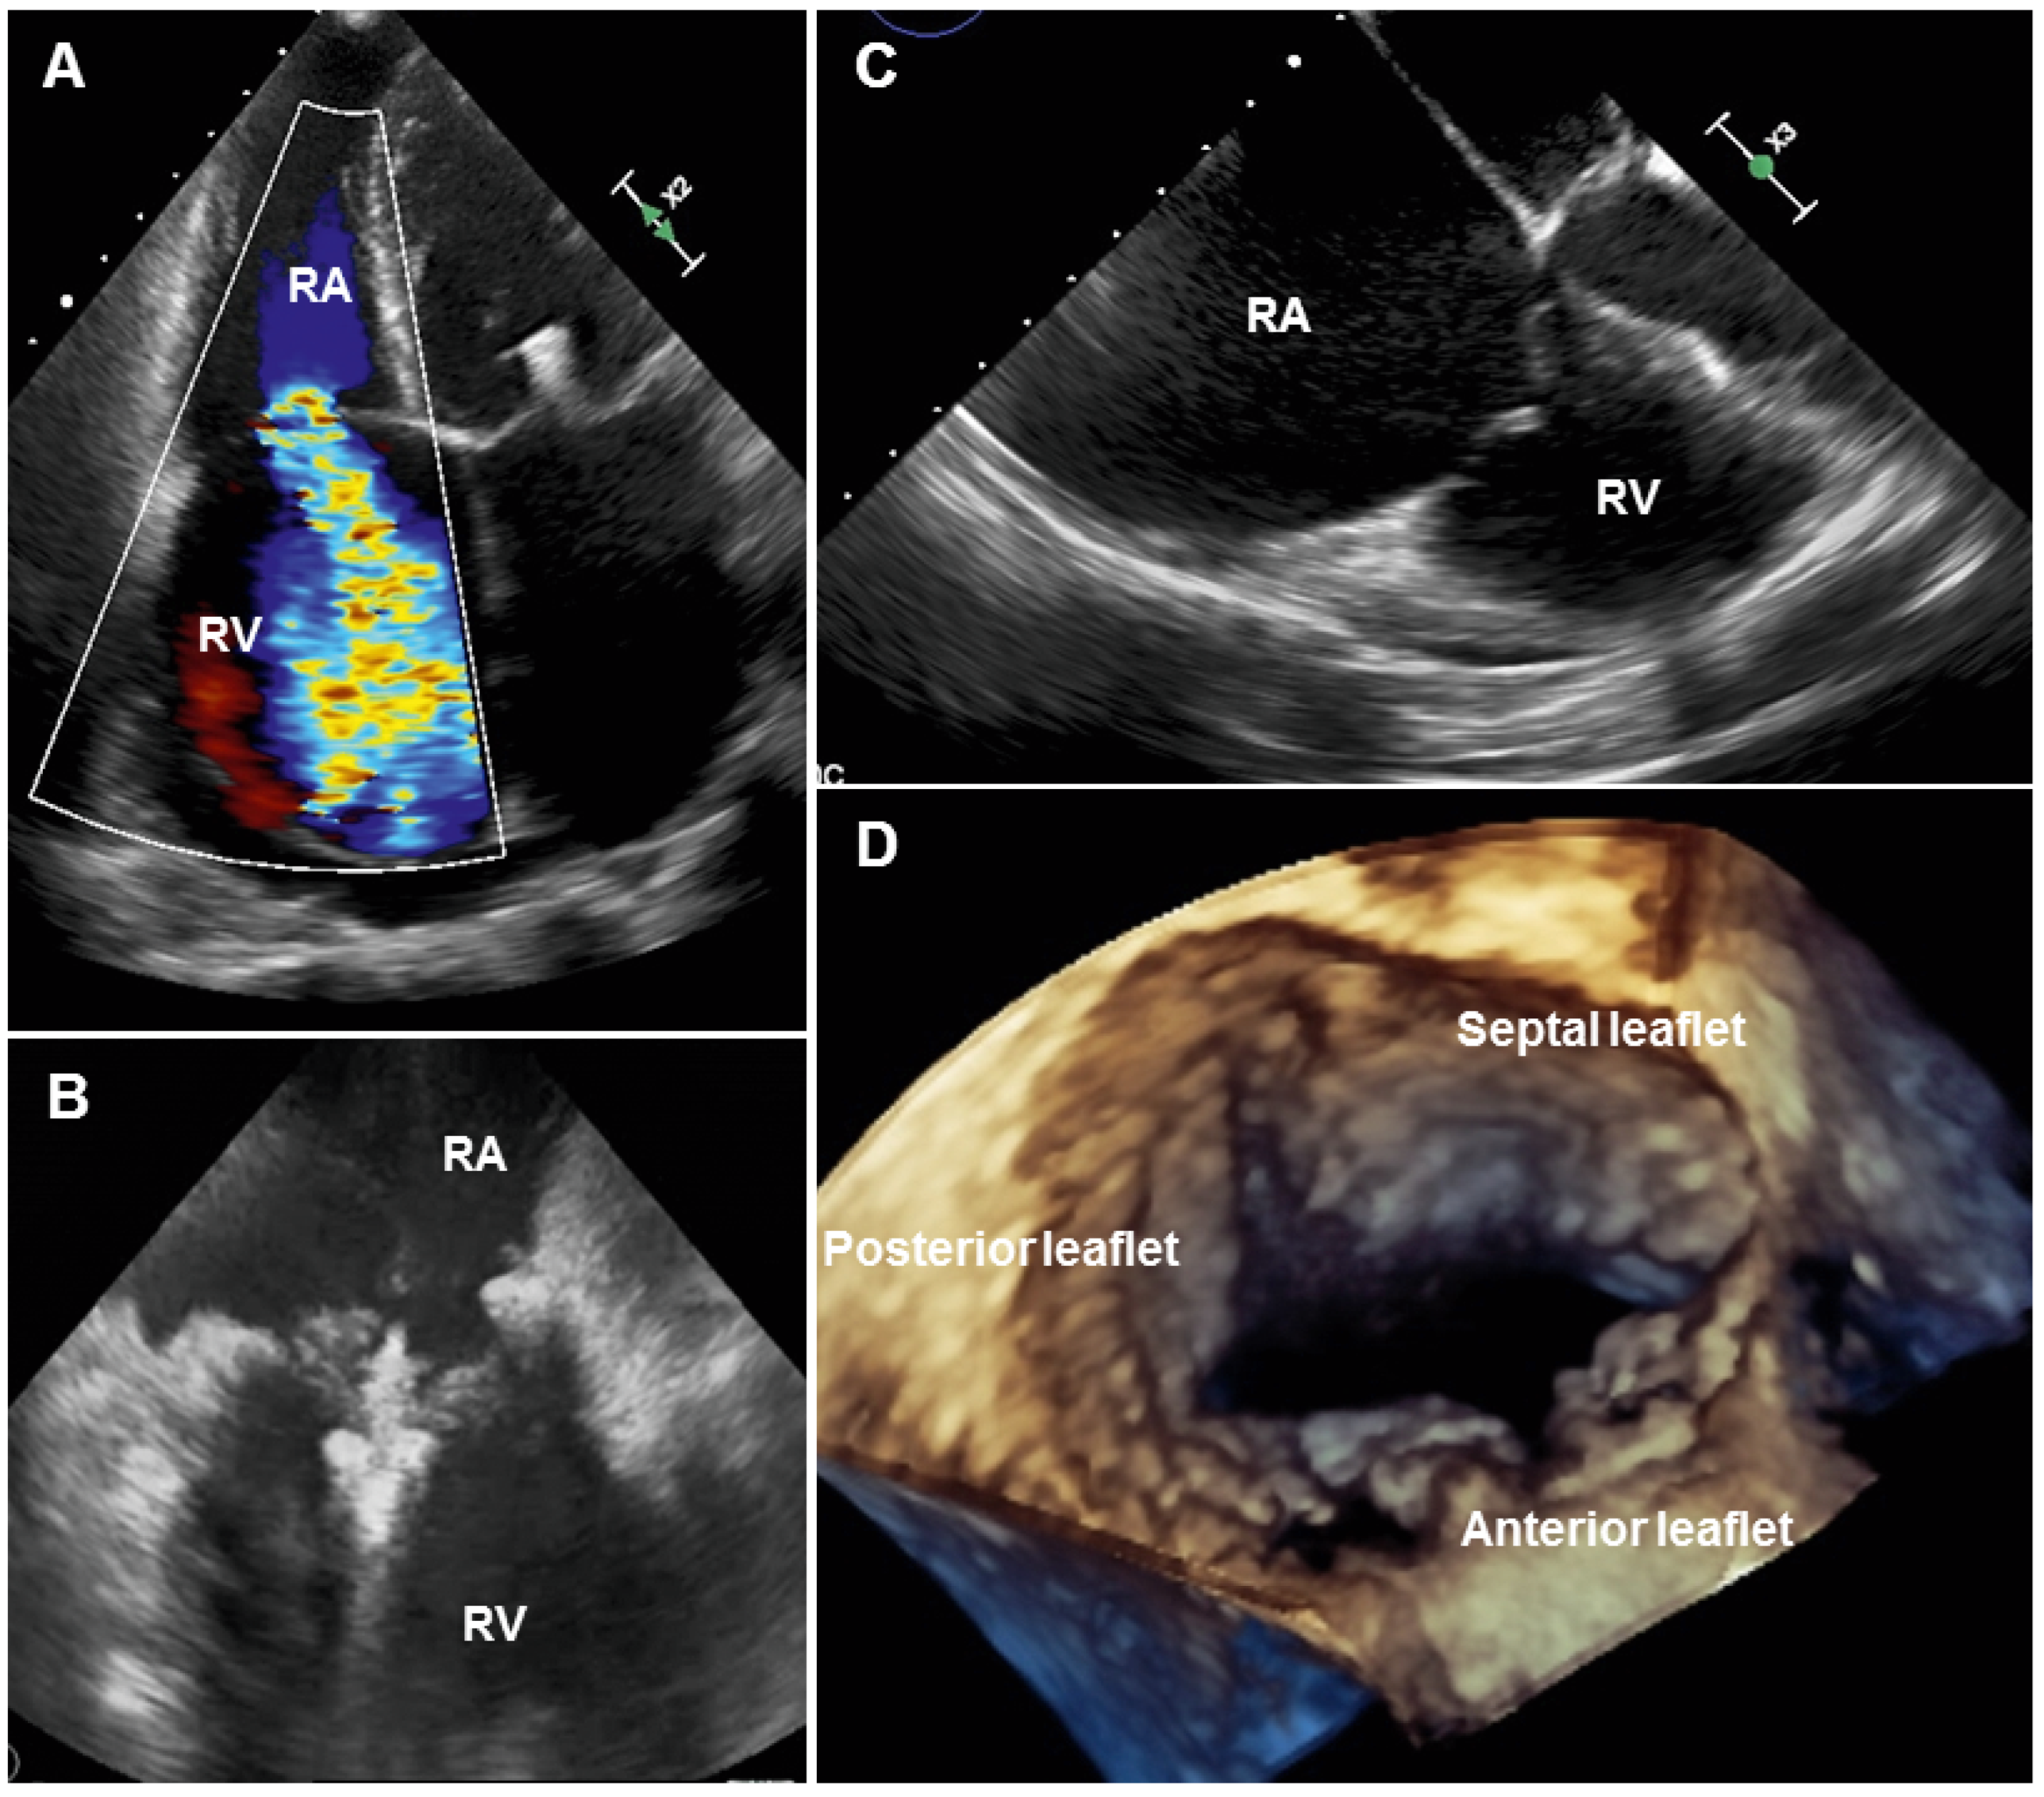

TR assessment with multi-imaging modalities